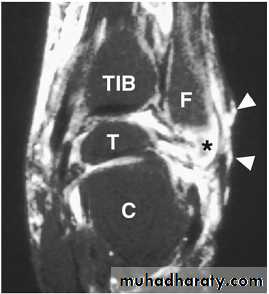

* Magnetic resonance imaging (MRI) is the most specific

and sensitive non-invasive test to evaluate OM and is

also useful for the evaluation of a probable abscess or

sinus tract formation.